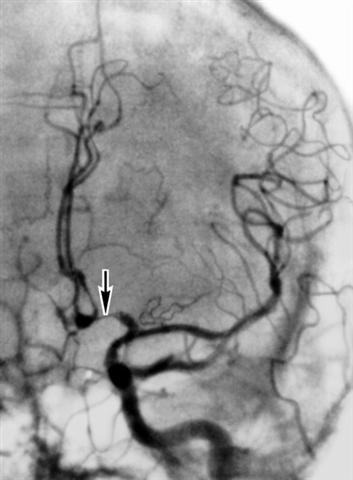

Рис. 3а). Каротидная ангиограмма (левосторонняя) больного с аневризмой передней соединительной артерии: выраженный спазм передней мозговой артерии (указана стрелкой) и умеренный спазм средней мозговой артерии.